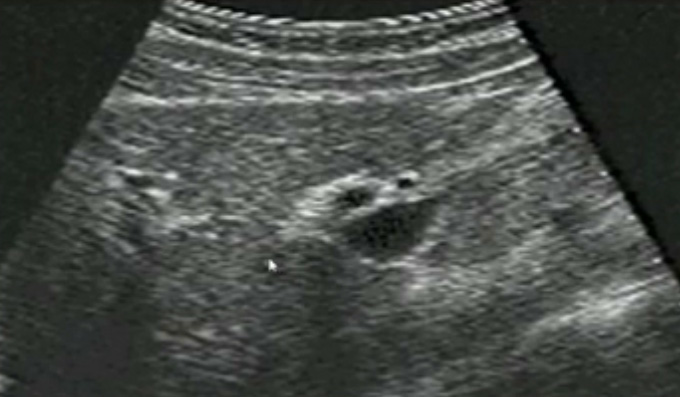

一、正常膽囊超聲圖像

膽囊的位置、形態(tài)、大小、壁厚,內(nèi)部及附壁是否有異?;芈?尤其膽囊要注意頸部,還要看有沒慢性炎癥的征象,腫瘤或隆起樣病變.正常膽囊聲像圖是像個瓣,膽囊正常大小,頸部指向肝門膽囊輪廓清晰,壁薄很光滑呈線狀,囊內(nèi)無回聲,后壁回聲增強(qiáng)。為什么無回聲呢?因?yàn)槟懼且后w,水,血液這些都是無回聲的。膽囊頸和門靜脈或門脈右支根部之間有一線狀高回聲帶連結(jié),這是識別膽囊位置的重要標(biāo)志。膽囊長徑一般不超90mm;前后徑2030mm,不超過40m正常充盈膽囊壁厚<3mm。 膽囊皺褶非常常見,

有的時(shí)候經(jīng)常發(fā)現(xiàn)檢查不到膽囊,其實(shí)有幾種可能性,檢查人員的技術(shù)不過關(guān)沒發(fā)現(xiàn)膽囊,就要找上級醫(yī)生會診,如果還是沒找到的話就不是技術(shù)問題。結(jié)石或腫瘤充滿膽囊,使其液腔消失,慢性膽囊炎使得膽囊萎縮或膽囊壁肥厚而囊腔消失患者已進(jìn)食,膽囊處于膽汁排空的狀態(tài),膽囊先天性過小或缺失;膽囊位置極端異常(可能很低或位于左側(cè))膽囊切除術(shù)后(注意詢問病史)。